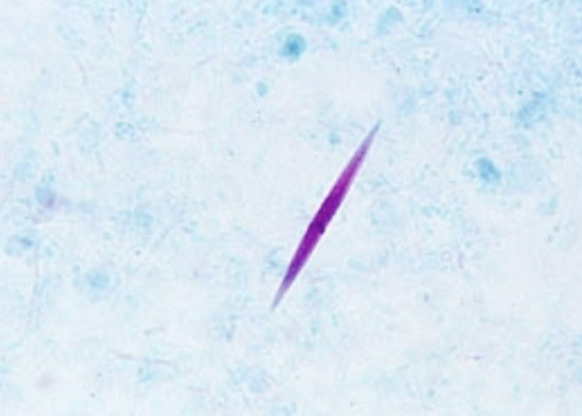

Charcot- leyden crystals

What is the result of broken down eosinophils associated with tissue invading parasitic infections?

Charcot-Leyden crystals